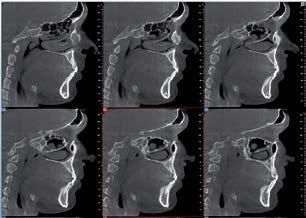

Nell’ambito della radiologia 3D ortopedica, il centro diagnostico utilizza il nuovissimo macchinario NewTom 5G XL, in grado di individuare con la massima precisione la presenza di fratture o lussazioni delle articolazioni, controllare la corretta guarigione di una frattura, valutare una lesione o una ferita causata da infezione, artrite o crescita anormale dell’osso.

Il tutto mediante una semplice e veloce scansione, grazie alla quale si otterranno diverse immagini in 3D ad altissima risoluzione e, per ottenere immagini ancora più nitide mediante un bassissimo dosaggio di radiazioni, gli esperti si avvalgono dell’innovazione racchiusa nella tecnologia Cone Beam.

Se con la radiologia tradizionale era necessario eseguire scansioni multiple, la novità introdotta dal macchinario NewTom 5G XL risiede nella capacità di fornire immagini ad alta risoluzione in un’unica scansione, mostrando nitidamente i dettagli delle articolazioni degli arti superiori e inferiori. Inoltre, a differenza della tecnologia 2D, la radiologia 3D ortopedica permette di individuare immediatamente alcune patologie come quella del metatarso, la quale richiede un allineamento visivo dedicato o una diagnosi delle micro fratture ossee.